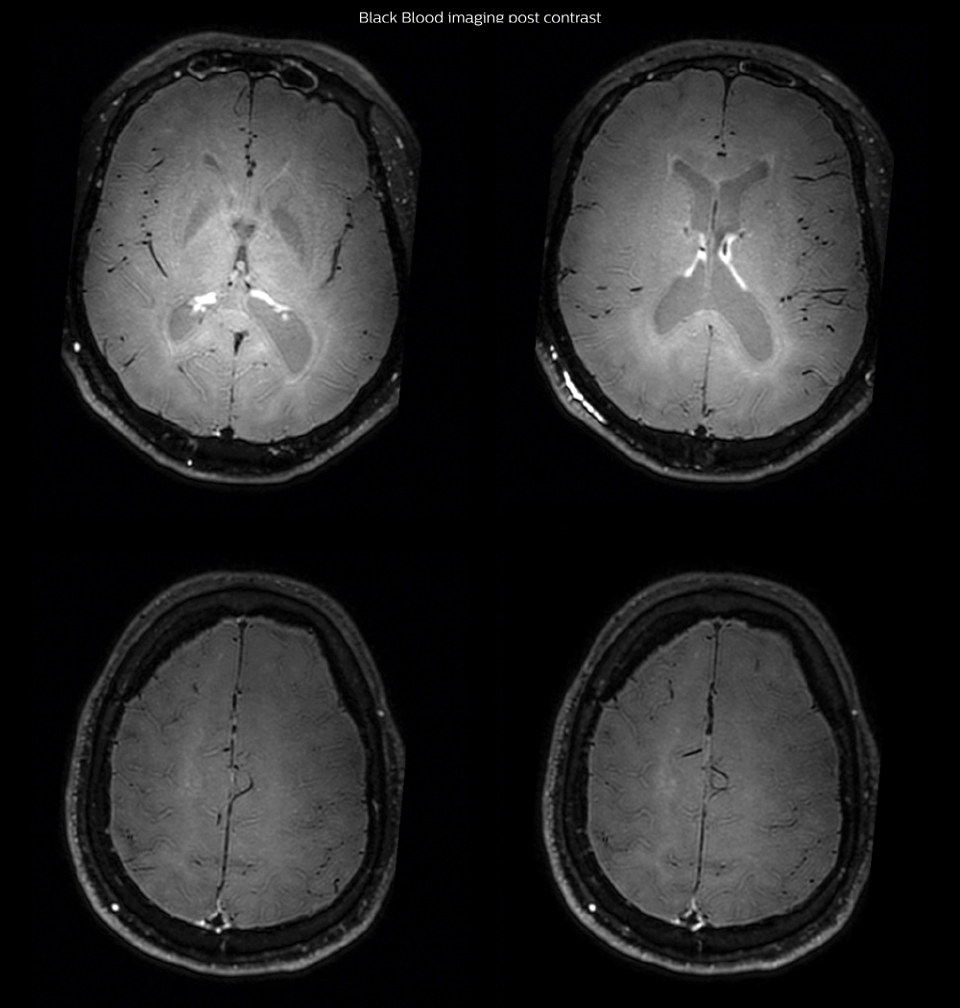

On FLAIR images we can see some nonspecific high signal abnormalities in frontal white matter bilaterally. On DWI we can see acute ischemic lesions which appear with high signal intensity. Arrows show vessel wall enhancement which appears concentric and homogeneous in different cerebral territories.

On the routine MR sequences that we did, we could see acute ischemic lesions. We see them very well on the diffusion images, where acute ischemic lesions usually appear with high signal intensity and restricted diffusion. However, the etiology of these lesions cannot be derived from these images. An area of restricted diffusion was seen in the anterior cerebral artery territory and we concluded it was an ischemic lesion. On MR angiography we can just see if there is stenosis or vessel occlusion, but it does not provide us information on the etiology of this kind of lesion. So, we decided to perform Black Blood imaging. The presence and the pattern of vessel wall enhancement on Black Blood imaging, can help us to determine the etiology of the lesion. differentiate vasculitis from other causes of vasculopathy, such as atherosclerosis, with a high specificity [1-3]. In an atherosclerotic lesion, vessel wall thickening and enhancement are usually eccentric, while in vasculitis the wall thickening and enhancement are usually concentric, homogenous, and in a long portion of the vessel. of patients whenever their treatment is installed in order to determine the efficacy of a particular treatment. In this case the Black Blood imaging helped us to suggest the diagnosis of HIV-related brain vasculitis.

had, such as glucose intolerance, arterial hypertension and hypocholesteremia, his lesions could be atherosclerotic lesions or vasculitis, conditions which require different treatment. Especially in this patient with HIV infection causing the vasculitis, treatment of the two conditions is different. The results of MRI with Black Blood imaging, helped to choose the preferred treatment for this patient, which was based on antiviral medication rather than an antiaggregant or anticoagulation treatment which is usually given to patients with risk of ischemia based on atherosclerotic lesions. One month after beginning the antiviral treatment, the same MRI examination was repeated and again 8 months after the beginning of treatment. On follow-up images, we see the enhancements have almost disappeared. So in case of this patient, the MRI exam with Black Blood imaging helped us to give the patient the appropriate treatment and also allowed us to noninvasively confirm the treatment response.

After one month of treatment, post-contrast Black Blood images at the exact same levels as in the figure above show disappearance of the vessel wall enhancements which were seen on the previous examination.